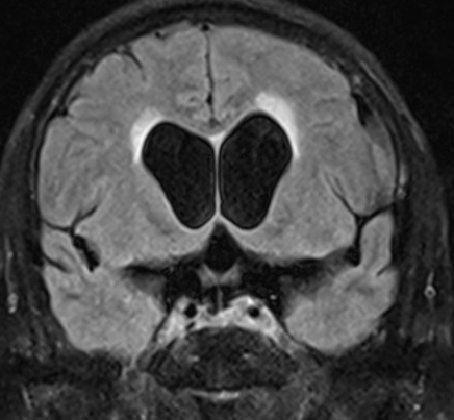

2015-4-1 MRI

2015-4-1

2015-4-3